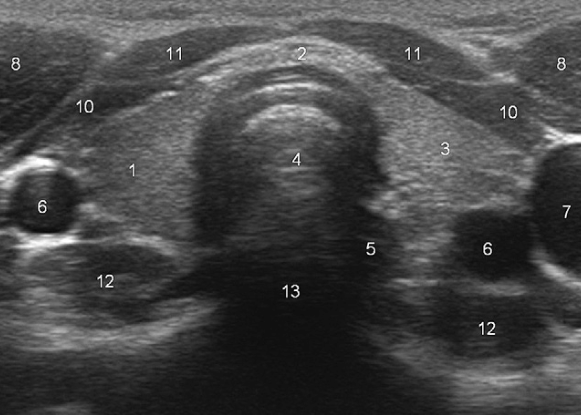

What does “5” represent?

Esophagus

What does “8” represent?

Sternocleidomastoid muscles

What do “10” and “11” represent?

Strap muscles (sternothyroid + sternohyoid)

What does “12” represent?

Longus colli muscles